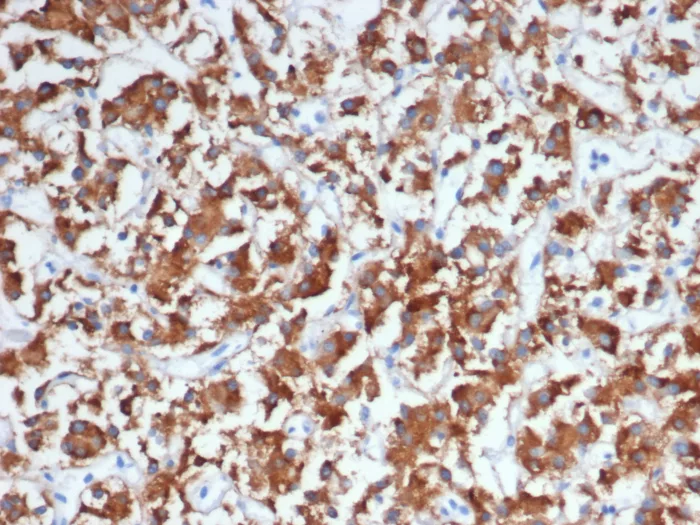

Immunohistochemistry (IHC)

1-2ug/ml

30 min at RT. Staining of formalin-fixed tissues requires heating tissue sections in 10mM Tris with 1mM EDTA, pH 9.0, for 45 min at 95°C followed by cooling at RT for 20 minutes

Human adrenal gland or adrenal pheochromocytoma.